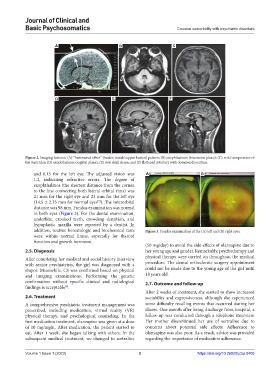

Figure 2. Imaging features: (A) “hammered silver” (beaten metal/copper beaten) pattern; (B) exophthalmos (transverse plane); (C) mild compression of

the ventricles; (D) exophthalmos (sagittal plane); (E) oval skull shape; and (F) flattened pituitary with downward position.